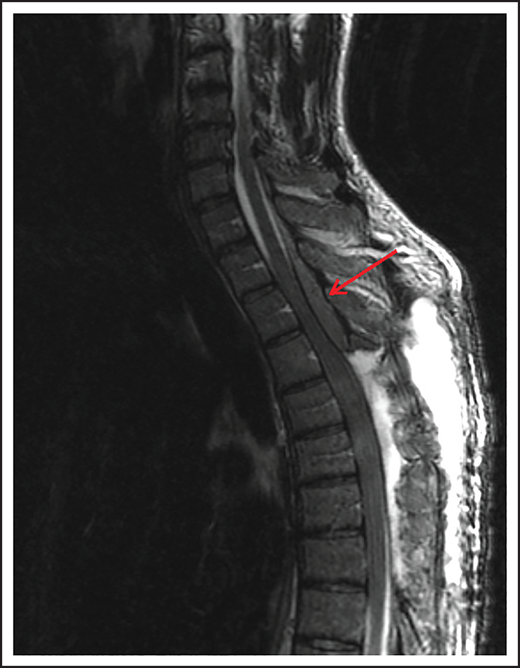

A 74-year-old man with a history of DLBCL treated with R-CHOP presented with progressive confusion and right-side weakness. A brain MRI demonstrated a contrast-enhancing lesion in the corpus callosum with extension into the left parietal region. A biopsy of the enhancing lesion confirmed a diagnosis of DLBCL. No other sites of disease were identified, and he was diagnosed with isolated CNS relapse. He was treated with HD-MTX, rituximab, and temozolomide for 4 cycles, and he achieved a complete radiographic response. Three years later, he presented with progressive memory loss, urinary incontinence, and gait ataxia. A brain MRI demonstrated periventricular white matter T2/FLAIR hyperintensities (Figure 3). Evaluation for toxic and metabolic causes of his symptoms was negative. His diagnosis was MTX-induced leukoencephalopathy.

Brain MRI of a patient with leukoencephalopathy caused by use of HD-MTX. An axial T2 fluid attenuated inversion recovery (FLAIR) image shows periventricular hyperintense signal reflecting leukoencephalopathy.

HD-MTX as well as IT MTX can cause acute as well as subacute encephalopathy.57,58 Acute encephalopathy is usually reversible. Subacute, or chronic, encephalopathy, as seen in case 4, is typically progressive, irreversible, and associated with high morbidity and mortality. It is a diagnosis of exclusion and as described in case 4, other causes must be excluded. The risk is higher with older age and when combined with whole-brain radiation therapy (WBRT).59